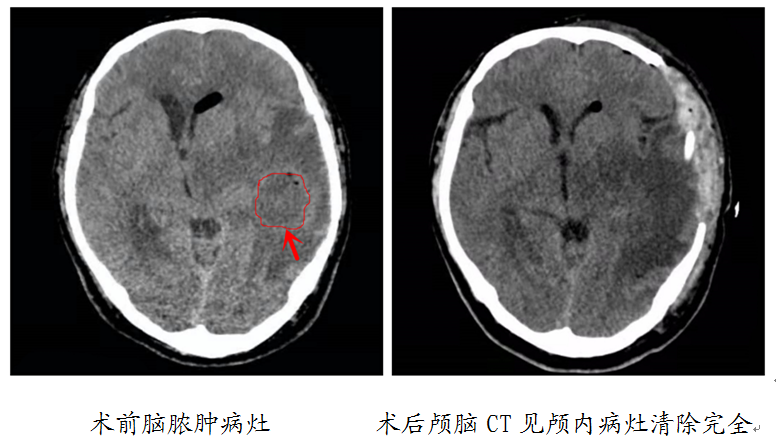

患者刘先生数日前患上了中耳炎,由于觉得是小病所以迟迟未到医院进行系统治疗。随着病情发展出现寒战、高热、谵妄、恶心、呕吐,并逐渐发展为意识障碍,这才在家属的陪同下到烟台山医院就诊。神经外科施宏志副主任医师、薛昆主治医师在了解病人病史、查体、阅读颅脑CT后初步诊断该患者是由中耳炎引起的颅内感染。脑疝是一种可能迅速致死的急危重症,考虑到患者入院时已脑疝,施宏志决定为其急诊实施“去骨瓣减压术”;但针对于病人颅内的脑脓肿感染灶若是实施感染灶切除,容易导致感染的扩散和病人颅脑的损伤,综合考虑后决定实施“脑内脓肿穿刺术”以规避风险,取得最佳治疗效果。脑内脓肿穿刺术的难点在于穿刺深度以及位置的确定,作为临床经验丰富的神经外科医师,施宏志及薛昆术前通过颅脑CT运用方体定向技术,精准施治,一针见脓。手术十分成功,术后经过一段时间的药物治疗之后,患者恢复了健康。

术中从颅内抽出的脓液。